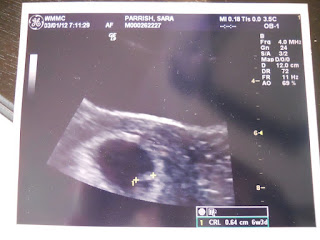

This is our first look at baby. 6 weeks and 3 days there. Size of seasame seed and you can still see it! Crazy!